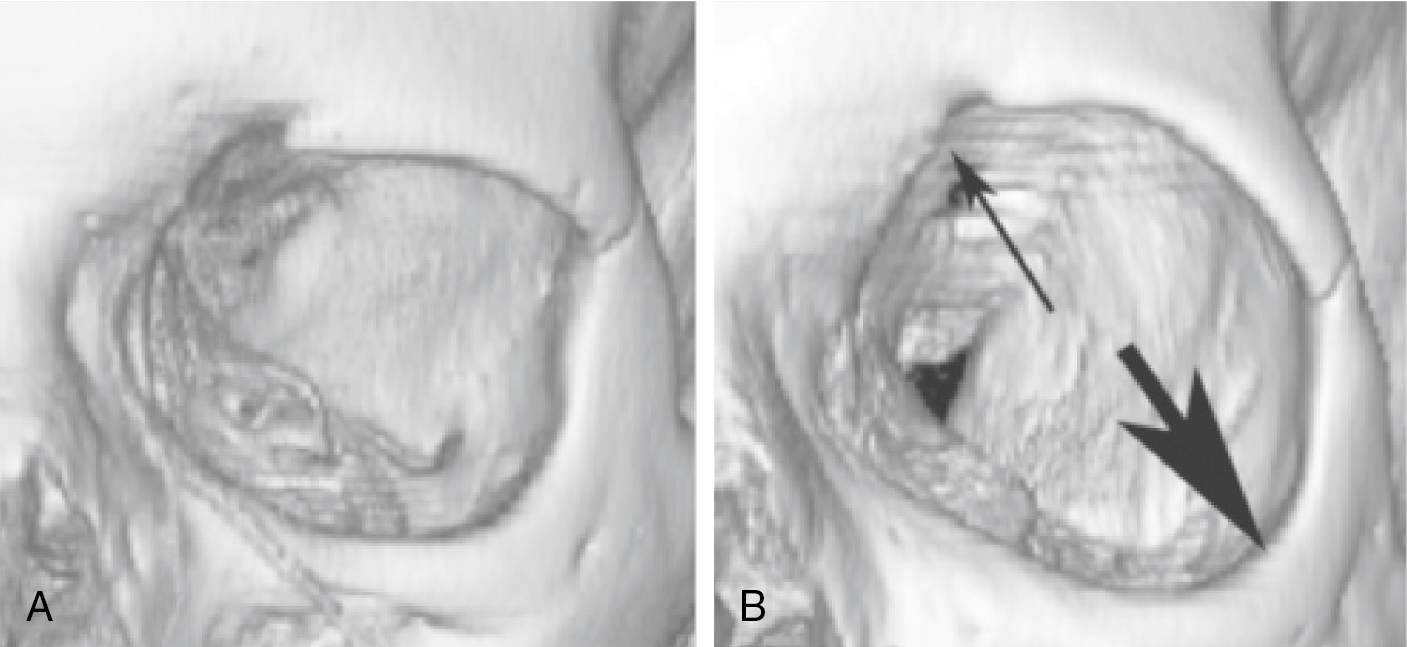

The supraorbital rim underlies the eyebrow and defines the upper limit of the orbit and upper lid sulcus. The septum orbitale attaches circumferentially around the orbit at the arcus marginalis and defines both the entry to the orbit and the retroseptal space. The supraorbital rim can be relatively low and flat (a masculine trait), or it may be arched, thus opening the upper lid sulcus. In a person with a low-lying transverse supraorbital rim, the upper lid sulcus will appear closed with minimal tarsal show, whereas the highly curved supraorbital rim creates a more open, hollow-looking upper lid sulcus with significantly more tarsal show. Rarely, in young people, a congenital arched supraorbital rim and upper sulcus hollowing may be a cause for concern. However, in the aging patient, there is a gradual enlargement of the orbit ( Fig. 38.3 A, B). This skeletal change, along with loss of upper sulcus fat, can lead to excessive openness and a hollow appearance in the upper sulcus, which will, in some patients, be a significant change from their youthful appearance. When combined with a congenital tendency for an arched supraorbital rim, this condition can be marked—an appearance sometimes referred to as “nursing home eyes.”